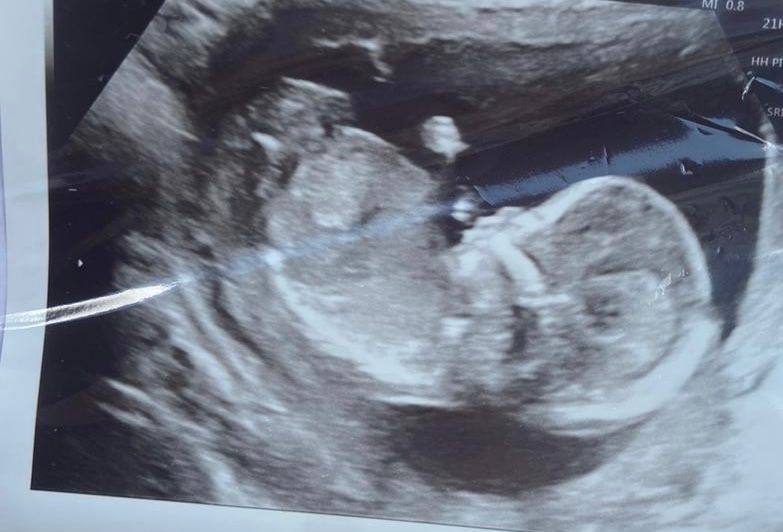

Пол ребёнка

Не видно же пол))

Сказала, что пока не понятно

а узист что предположила?